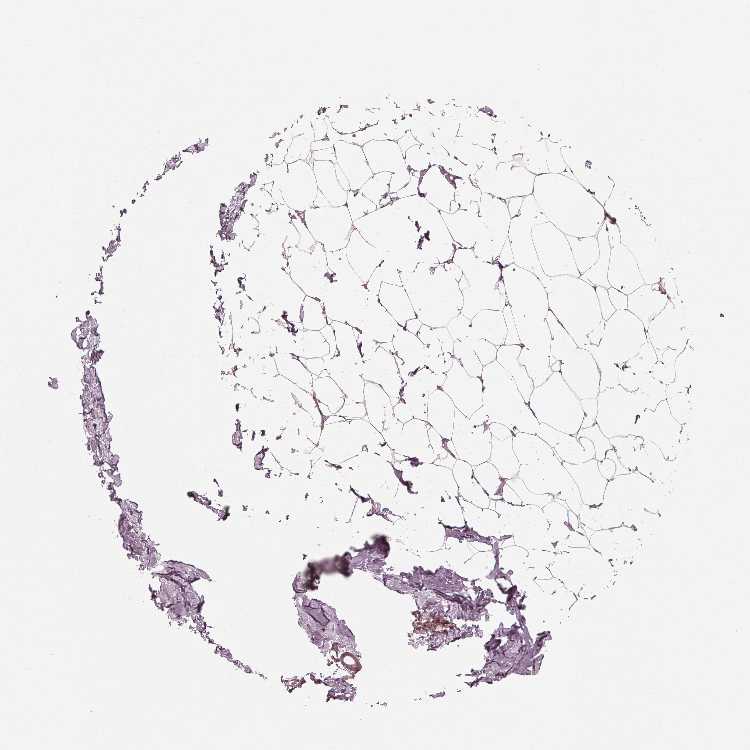

TISSUE PRIMARY DATA BREAST Show tissue menu

BREAST - Antibody stainingi

Antibody staining in the annotated cell types in the current human tissue is reported as not detected, low, medium, or high, based on conventional immunohistochemistry profiling in selected tissues. This score is based on the combination of the staining intensity and fraction of stained cells.

Each image is clickable and will lead to virtual microscopy that enables deeper exploration of all samples and also displays staining intensity scores, fraction scores and subcellular localization as well as patient and tissue information for each sample.

Antibody HPA066771

Adipocytes Not detected

Glandular cells Not detected

Myoepithelial cells Not detected